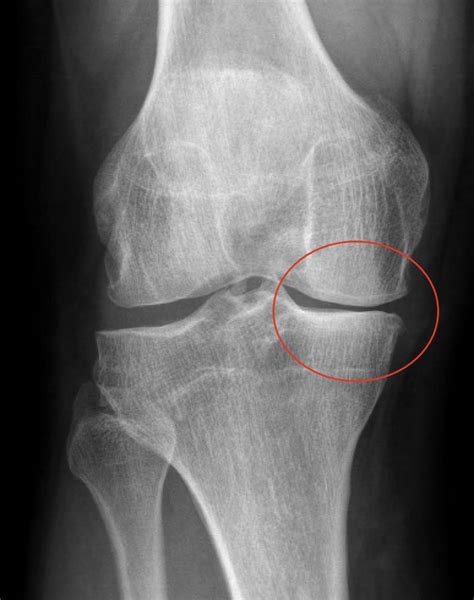

De verdunning van het kraakbeen wordt opgedeeld in verschillende graden van lichte graad (graad 1: verdunning/uitrafeling van kraakbeen) tot volledige slijtage (graad 4: geen kraakbeen meer aanwezig, zogenaamd bot-op-bot contact) Artrose aan de knie wordt ook wel gonartrose genoemd

Bij een knieprothese wordt het gewricht vervangen door metalen platen die in het bot wordt geplaatst Omdat in het kraakbeen heel erg weinig pijnreceptoren zitten, kan het niet direct pijn registreren. Dat zorgt voor pijn en kan zelfs een hoorbaar krakend geluid veroorzaken

MRI anatomie knie, enkel en voet benaming vlakken Hoe ziet het bot eruit op de volgende. Hoewel osteoartritis voornamelijk bij ouderen wordt gezien, kan het al vanaf de kindertijd beginnen, omdat het kraakbeen op lange termijn slijt. Het is een beschermingsreactie van het lichaam tegen artrose, om de extra druk die wordt veroorzaakt te verdelen over een breder vlak.